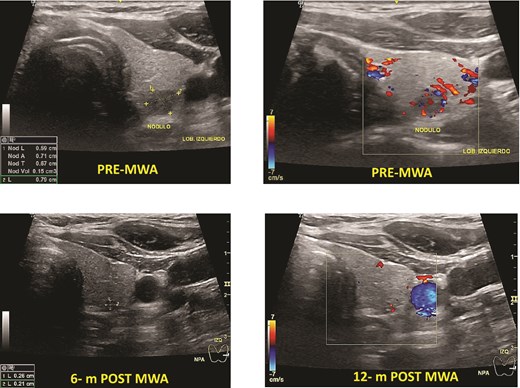

One patient had PTC. The mean baseline volume was 0.13 mm. After ablation, the mean volume at 1-month follow-up was 0.05 ml, and after 12 months, it disappeared. There was no local tumor progression or lymph node metastasis (Fig. 2).

Papillary thyroid microcarcinoma pre- and post-MWA (6 and 12 months). Note that the nodule’s vanishing, making it hard to identify it by ultrasound.